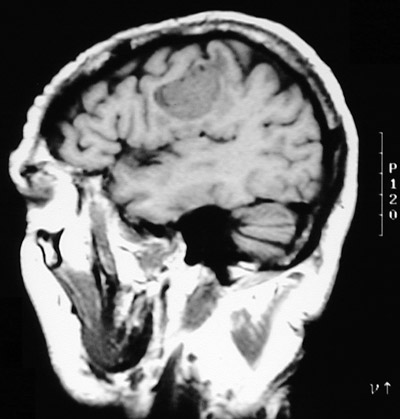

| These T1 weighted MRI scans in axial view above and sagittal view below demonstrate a solitary mass with minimal adjacent edema located in the cortex near the grey-white junction. This lesion in a middle aged male proved to be a metastasis from a pulmonary adenocarcinoma. |